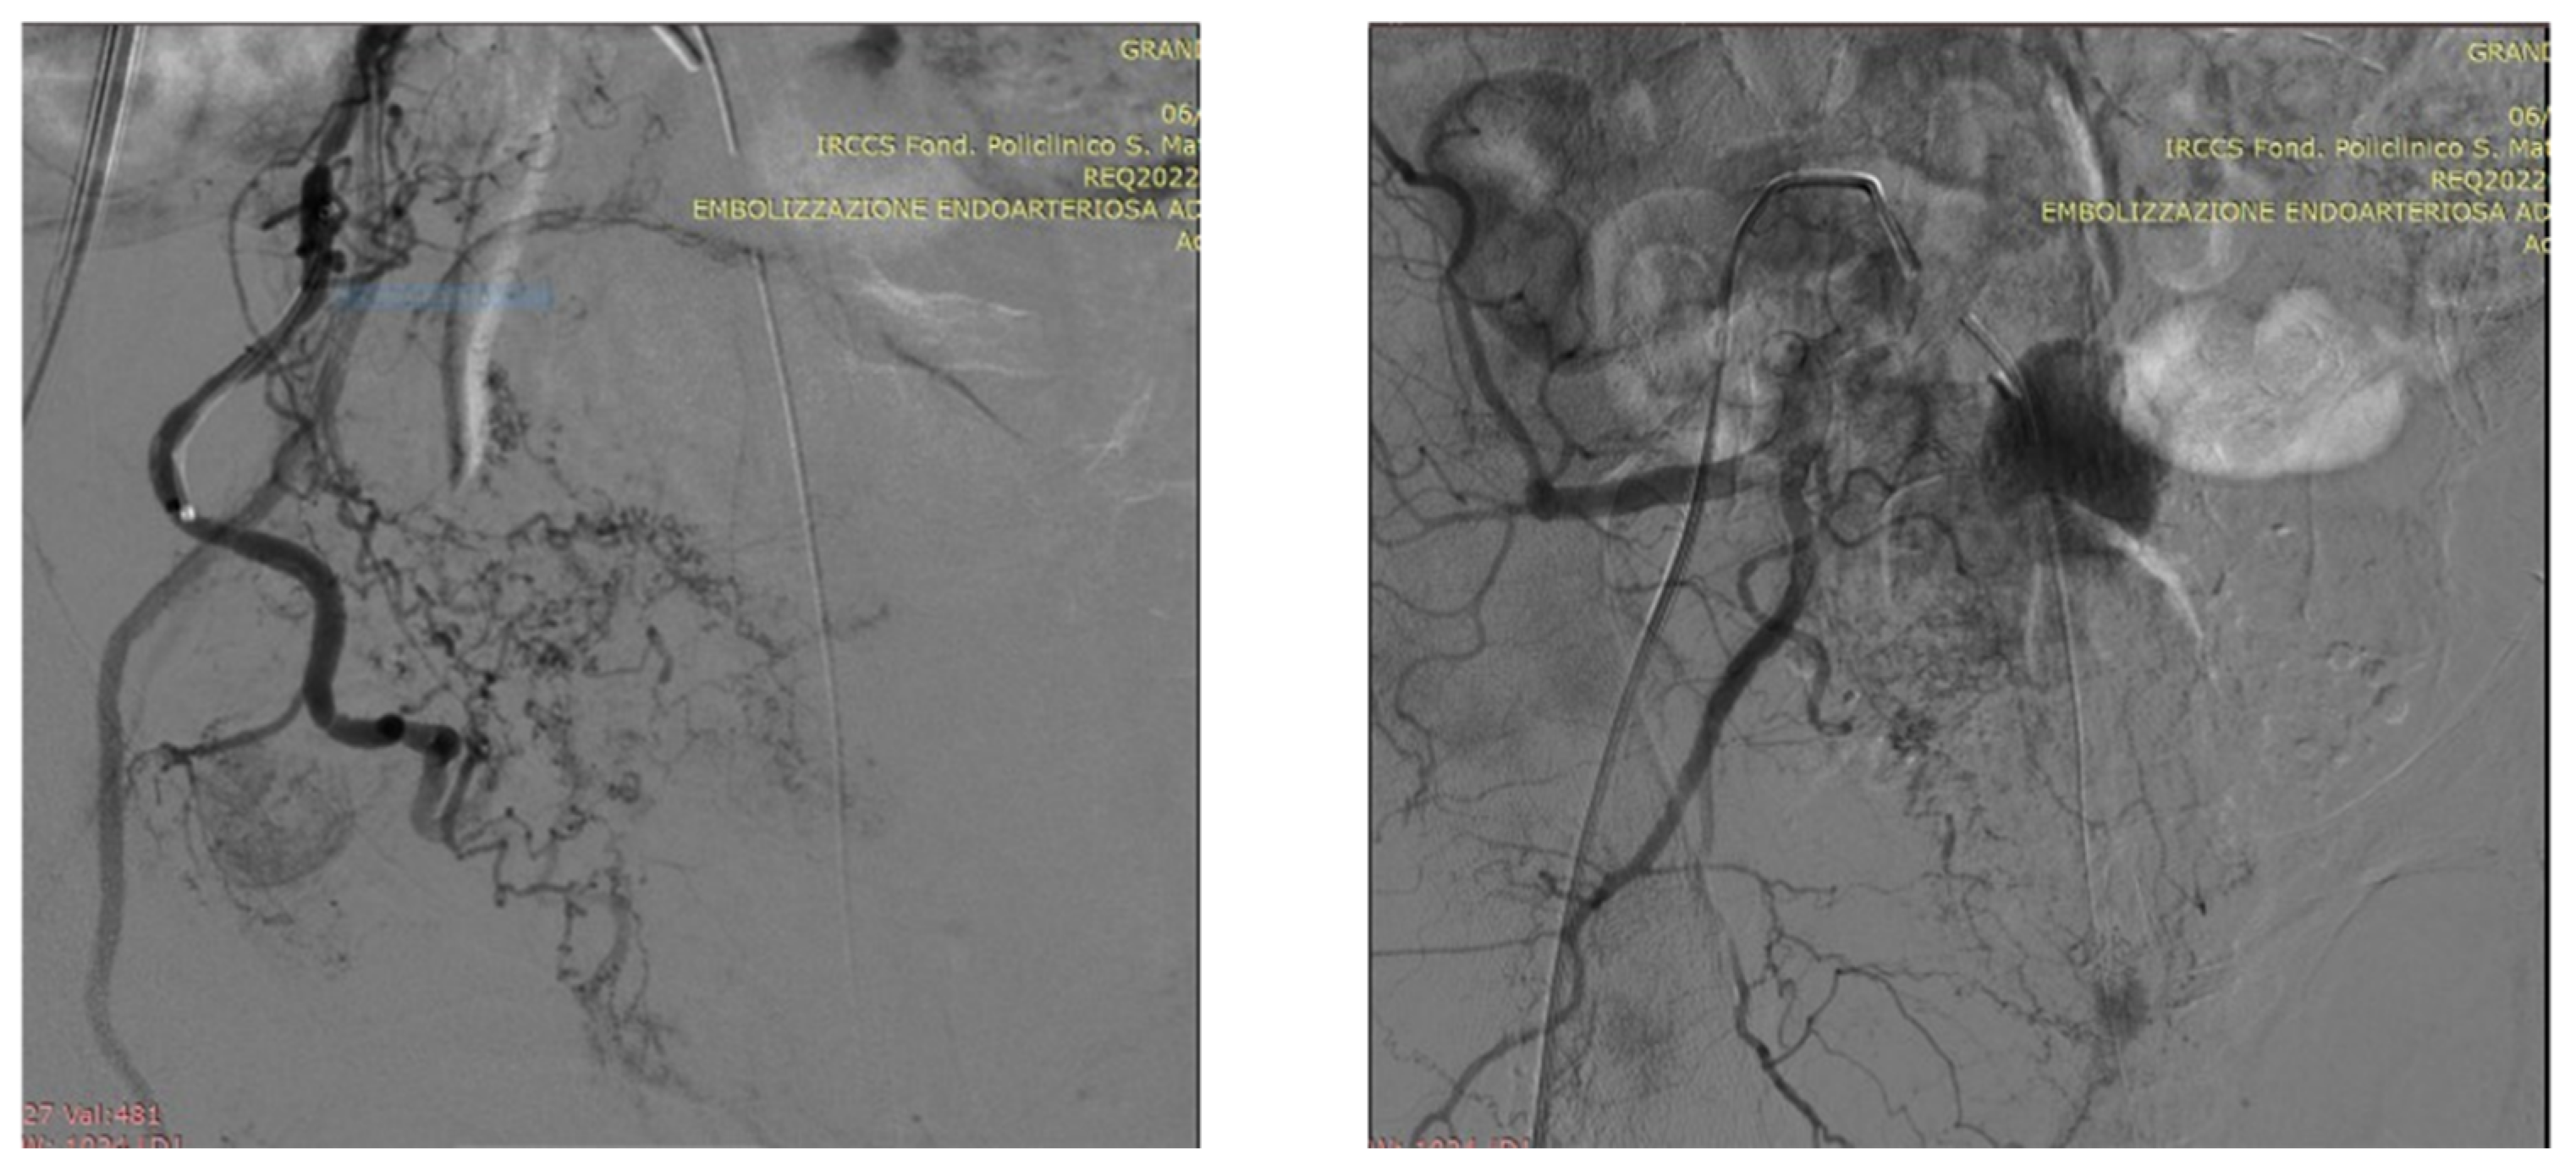

5. A Suggested Algorithm and a Demonstrative Case Report

Technical Details of PAE